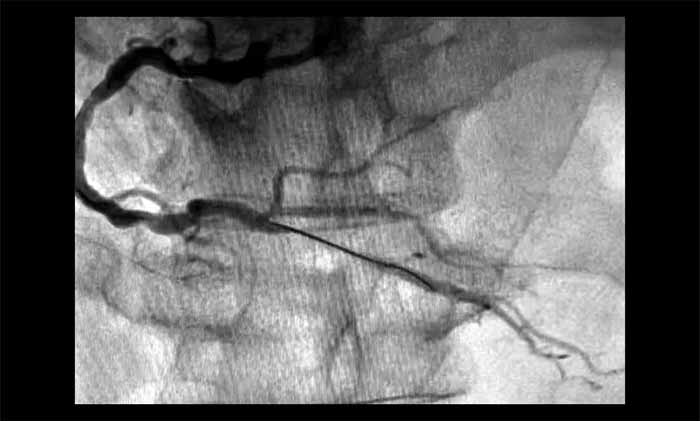

▲ 术前,RCA中段严重狭窄(约95%)伴血栓

▲ 术后,血管顺利开通

1月28日,姜朝晖博士团队为患者行冠状动脉球囊扩张及支架植入。术中,行多角度造影提示RCA中段严重狭窄近95%,并伴有血栓。通过及时介入,开通闭塞血管,恢复了心肌供血。